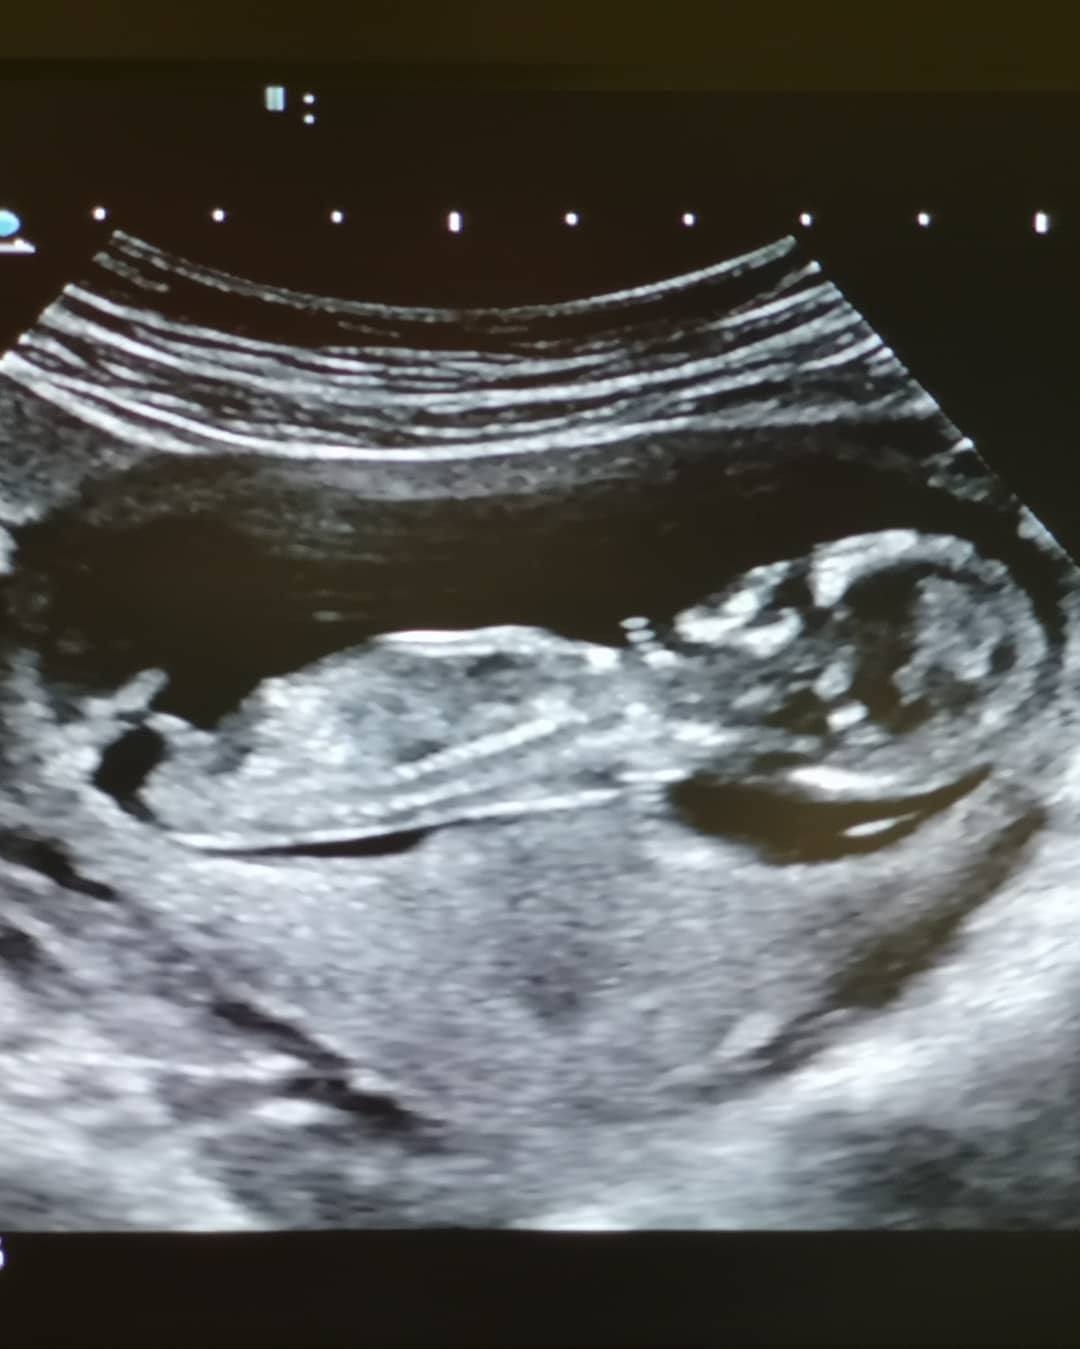

ทั้งนี้ กิก ดนัย ได้โพสต์ภาพคู่กับภรรยา โชว์ภาพอัลตราซาวด์ พร้อมข้อความว่า "สุขสันต์วันเกิดนะครับน้องแนน คู่หูคู่ชีวิต ขอให้มีความสุขมาก ๆ สุขภาพแข็งแรง ครอบครัวสุขสันต์ สมหวังทุกเรื่อง ปีนี้เรา 2 คน ไม่มีของขวัญให้กัน เพราะคงไม่มีสิ่งไหนมีค่าเท่ากับสิ่งที่จะเกิดขึ้นมาในปีนี้ แล้วเจอกันนะไอ้ลูกชาย"